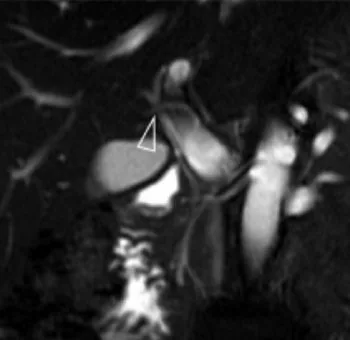

Figure 11. Dilatation des voies biliaires intra-hépatiques postérieures droites,

dont la lumière est remplie par de multiples calculs (tête de flèche).

Un cathétérisme rétrograde a été réalisé, avec des prélèvements

cytologiques par aspiration de bile et brossage biliaire. Les calculs n’étaient

ici qu’une conséquence et non la cause de l’obstruction : la cytologie a montré

la présence d’un cholangiocarcinome sous-jacent